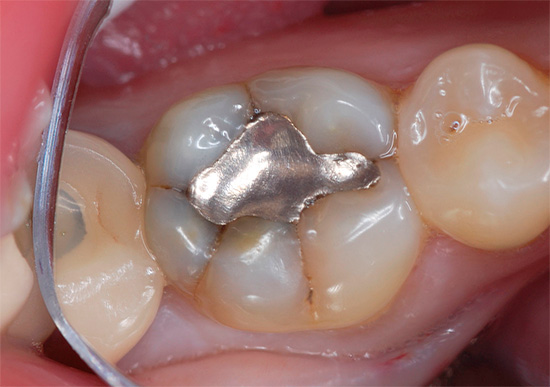

Um tipo obsoleto de material de enchimento são as amálgamas (prata e cobre). Não podem ser utilizados nos dentes da frente, por não serem estéticos, portanto a área de uso é nas classes Black 1, 2 e 5, bem como nos dentes cobertos com coroas.

É interessante

Para o tratamento de cárie profunda no século XX, as amálgamas eram um material de enchimento indispensável que ainda é encontrado. Praticamente não há obturações, exceto amálgama, que possui uma existência segura de 20 a 30 anos no dente. O amálgama de prata é um selo metálico com um efeito antibacteriano ativo da prata (e mercúrio). As possibilidades de sua retenção são quase infinitas.

Infelizmente, na Rússia foi cancelada às pressas devido à probabilidade de infecção do corpo com mercúrio, uma vez que o pó de prata foi amassado nele.Os dentistas americanos provaram com sucesso o oposto: eles conduziram uma série de estudos e não identificaram a possibilidade de envenenamento por mercúrio, mesmo para a equipe, enquanto observavam os padrões de conservação. Segundo os dados mais recentes, desde 2000, os dentistas americanos vêm realizando anualmente uma amálgama para vários milhões de dentes. Na Rússia, o amálgama quase nunca é usado, embora o tratamento de cárie profunda com seu uso seja bastante eficaz.